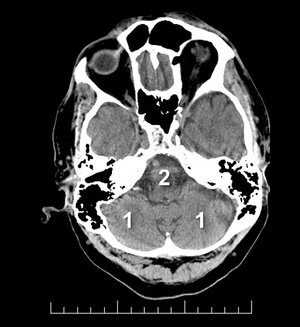

pc-ASPECTS — Niveau pontique : P (pont), C (cervelet)

Niveau pontique

P Pont (2 pts) · C Cervelet